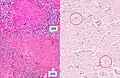

A case of miliary tuberculosis in an 82-year-old woman:

-

Gross pathology of the lung, spleen and kidney, showing micronodules (1–4 mm in diameter) which resemble millet seeds -

Histopathology, showing epithelioid granulomas with multinucleated giant cells and acid-fast bacilli